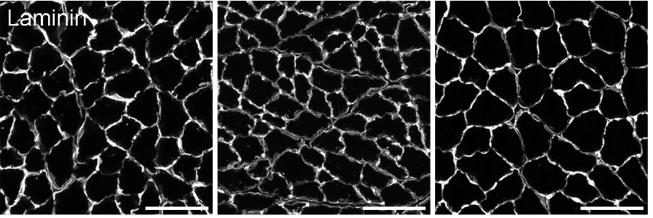

뇌-말초조직 네트워크 규명을 위한 신경회로 발굴 및 제어연구

근육-뇌, 지방조직-뇌 상호작용 제어를 통한 시스템 에너지대사 조절연구

- 연구주제 : 근육-뇌 신경회로 역할 규명을 통한 인지기능 및 근감소증 제어연구

- 연구주제 : 뇌혈관장애-유래 인지기능 저하 및 근감소증 제어기전 연구